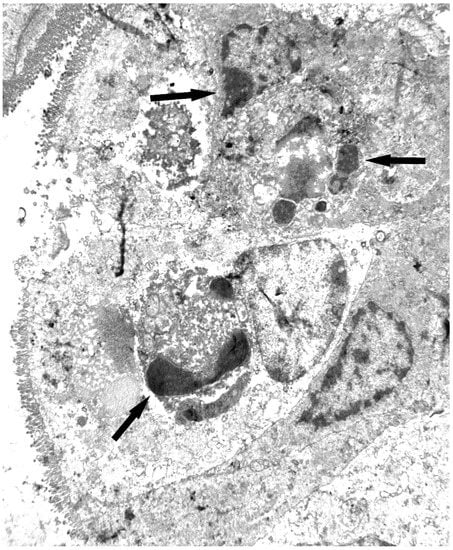

- Gayoso, M.J.; Muñoz, R.; Arias, Y.; Villar, R.; Rojo, M.A.; Jiménez, P.; Ferreras, J.M.; Aranguez, I.; Girbés, T. Specific dose-dependent damage of Lieberkühn crypts promoted by large doses of type 2 ribosome-inactivating protein nigrin b intravenous injection to mice. Toxicol. Appl. Pharmacol. 2005, 207, 138–146. [Google Scholar] [CrossRef] [PubMed]

- Jiménez, P.; Gayoso, M.J.; Garrosa, M.; Cordoba-Diaz, D.; Cabrero, P.; Tejero, J.; Aracil, M.; Girbés, T. Paneth cells are also target of the ribotoxic lectin nigrin b. Histol. Histopathol. 2014, 29, 1057–1063. [Google Scholar] [PubMed]

- Jiménez, P.; Cordoba-Diaz, D.; Cabrero, P.; Aracil, M.; Gayoso, M.J.; Garrosa, M.; Cordoba-Diaz, M.; Girbés, T. Plasma accumulation of vitamin B6 from an oral dose in a new gut injury-regeneration reversible mouse model. Food Nutr. Sci. 2013, 4, 908–917. [Google Scholar] [CrossRef]

- Jiménez, P.; Cabrero, P.; Tejero, J.; Gayoso, M.J.; Garrosa, M.; Cordoba-Diaz, D.; Cordoba-Diaz, M.; Girbés, T. Concentrated extract of green tea polyphenols enhances the toxicity of the elderberry lectin nigrin b to mice. Food Nutr. Sci. 2014, 5, 466–471. [Google Scholar] [CrossRef]

- Battelli, M.G.; Citores, L.; Buonamici, L.; Ferreras, J.M.; de Benito, F.M.; Stirpe, F.; Girbes, T. Toxicity and cytotoxicity of nigrin b, a two-chain ribosome-inactivating protein from Sambucus nigra: Comparison with ricin. Arch. Toxicol. 1997, 71, 360–364. [Google Scholar] [CrossRef] [PubMed]